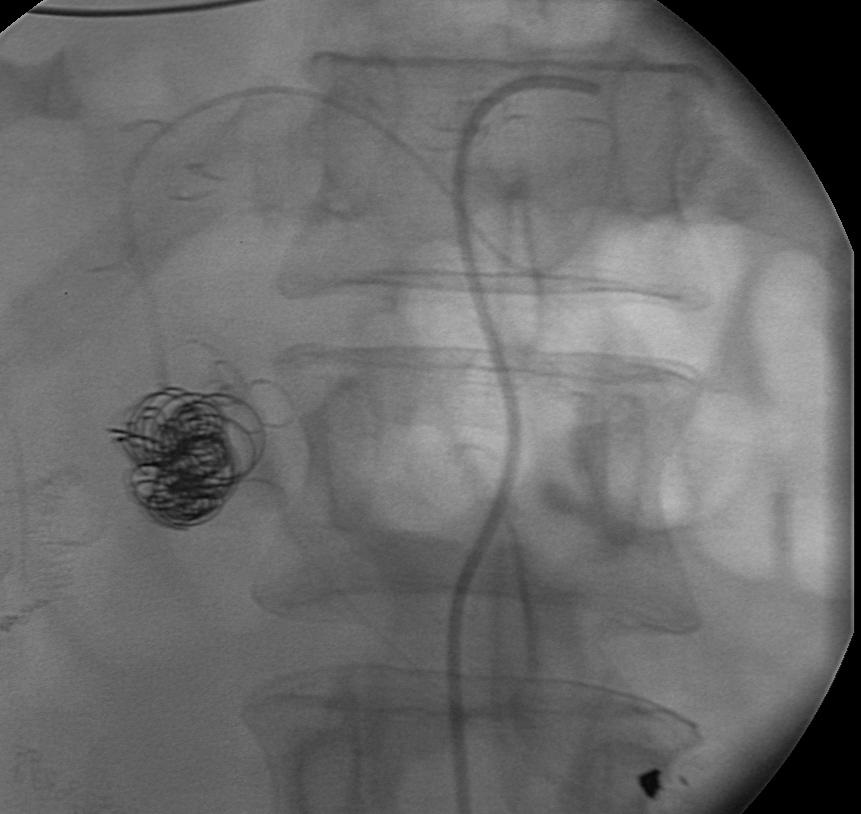

胰十二指肠动脉瘤占内脏动脉瘤2%。主要原因包括动脉硬化,腹腔动脉狭窄等疾病,后者是由于胰腺动脉弓的高血流状态(Sutton and Lawton 1973)。假性动脉瘤主要由于胰腺炎、创伤和感染(Suzuki et al. CVIR 2008;31:1082-1087)。 腹腔动脉闭塞导致胰腺血管弓

腹腔动脉闭塞导致胰腺血管弓的高血流状态致使胰腺动脉明显增粗 |

Suzuki 等人报告7例CT证实破裂动脉瘤病人,平均直径0.6mm。破裂与大小没有直接联系,18%的破裂动脉瘤<1cm。一般推荐在发现时就进行血管内治疗,但要考虑解剖情况和技术上的困难。